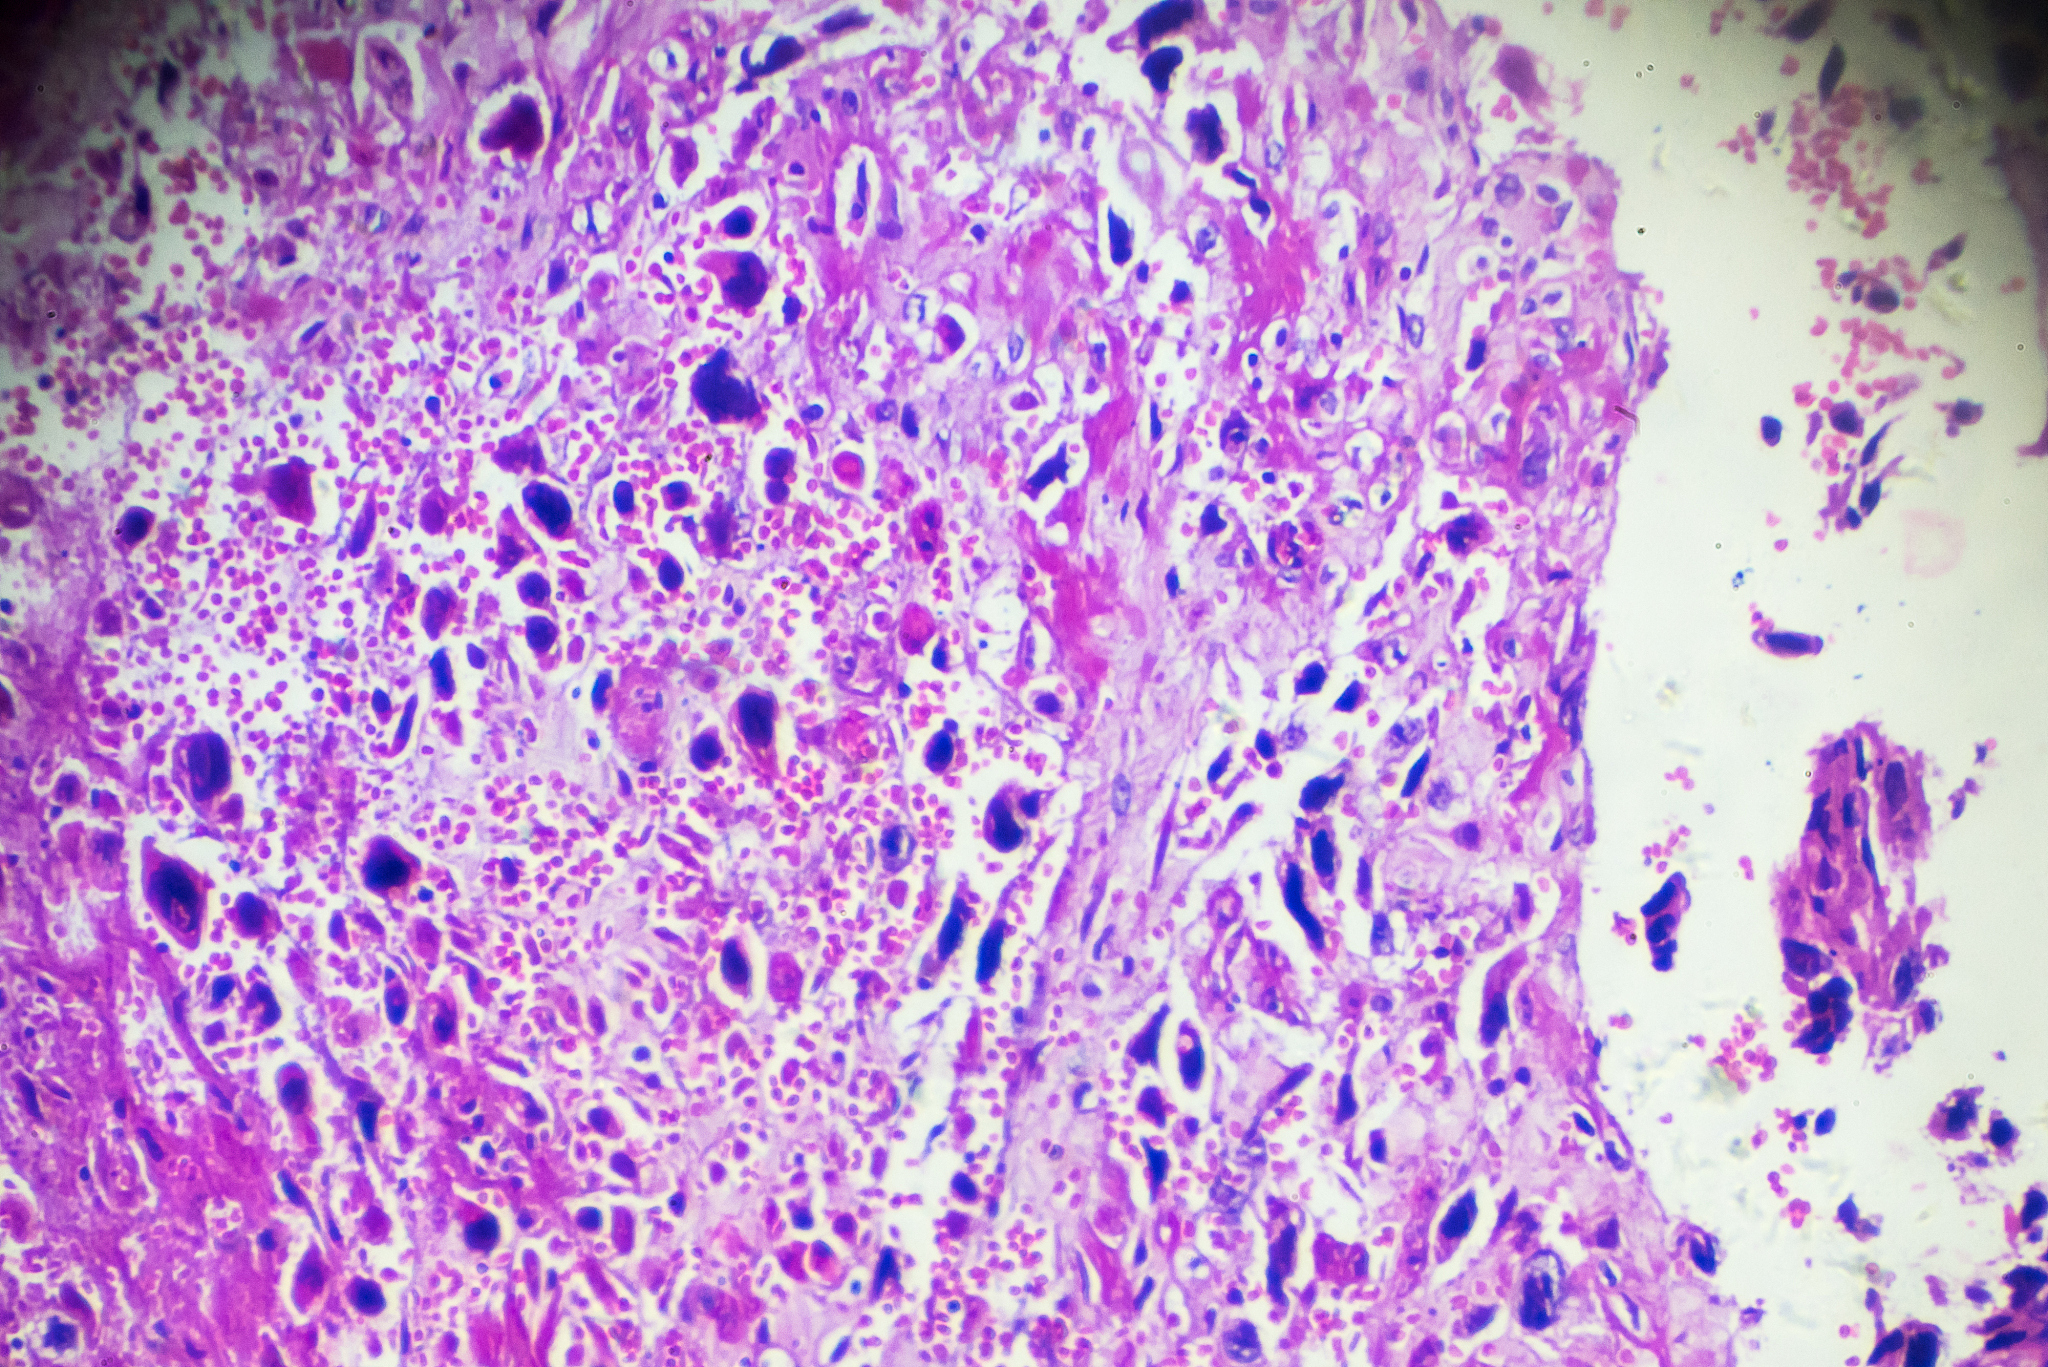

溃疡性结肠炎是一种病因尚不明确的直肠和结肠黏膜病症,常表现为腹痛、腹泻、黏液便和血便等症状。该疾病难以完全治愈,且存在癌变的风险,被世界卫生组织认定为现代难治病之一。

溃疡性结肠炎ulcerative colitisUC又称为慢性非特异性溃疡性结肠炎是一种至今病因尚不明确的直肠、结肠黏膜病症以腹痛、腹泻、黏液便、血便为常见的临床表现且病程迁延较难根治有癌变倾向已被世界卫生组织列为现代难治病之一。不改变大意换个说法